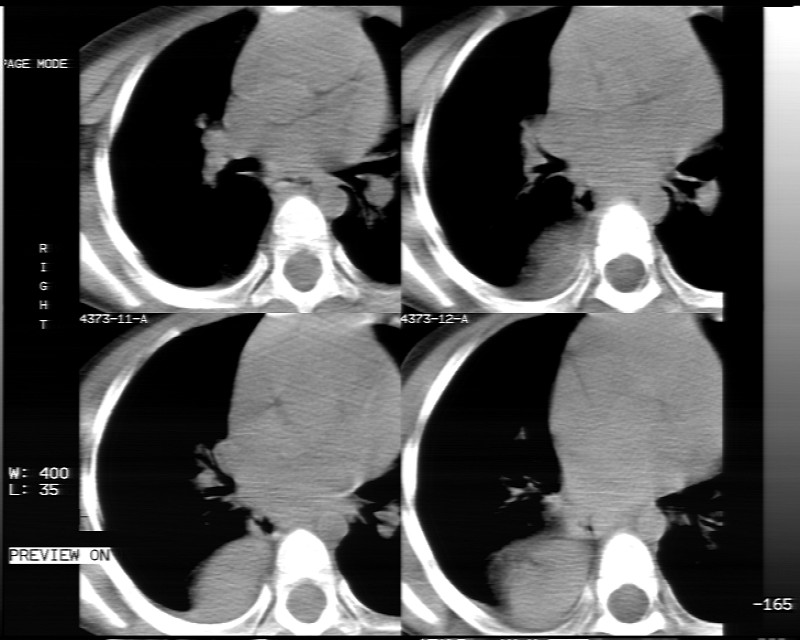

男性,3岁,斜疝术前常规检查胸片体检发现右下肺病变。咳嗽,无发烧。

象腹腔的东西,考虑膈疝

膈疝的表现

内有气体,液平面,考虑食管裂孔疝可能性大。建议食道钡透。

膈疝,可见黏膜·

有液气平面,前部肺纹理聚集(受压改变),周围肺野及相邻胸膜清晰,支持膈疝,可吞服造影剂看一下。

考虑膈疝(右侧胸腹膜裂孔疝?)。